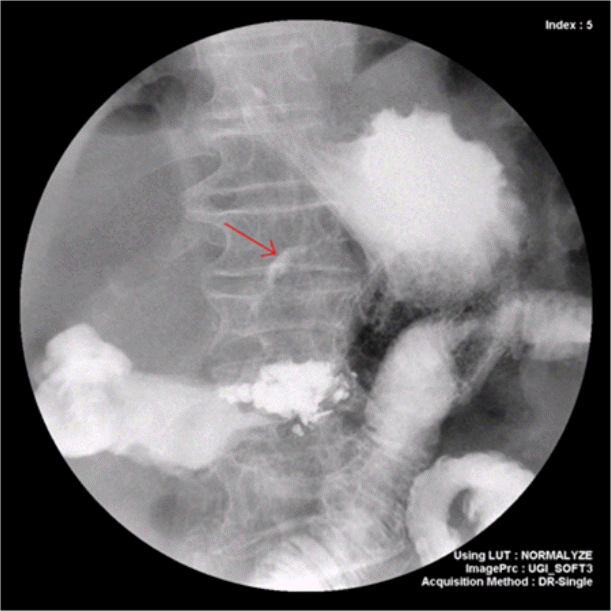

Figure 3.

Upper gastrointestinal series using gastrografin shows contrast agent leakage (arrow). A vertebroplasty lesion is evident at the L1 vertebra.